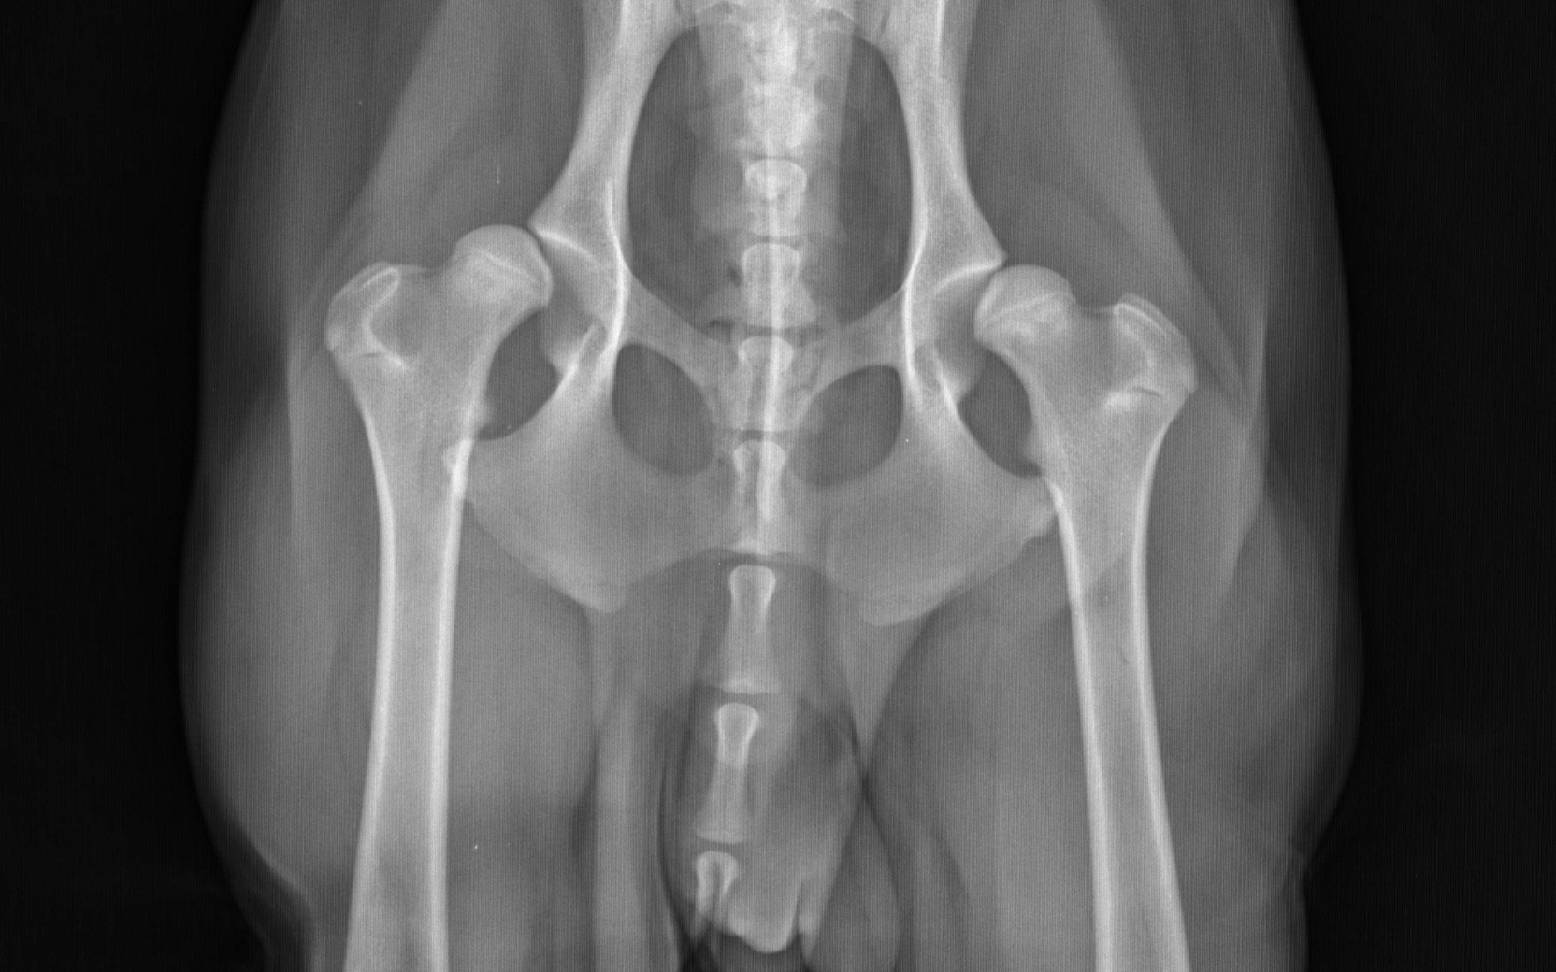

Dein/e Tierärzt:in kann anhand deines Vorberichts und einer eingehenden orthopädischen Untersuchung schon deutliche Hinweise auf das Vorliegen einer HD erhalten. Durch verschiedene passive Mobilitäts-Tests kann er/sie Schmerzhaftigkeit, Instabilität oder Bewegungseinschränkungen des Hüftgelenks feststellen. Der Verdacht einer HD kann allerdings nur mit Hilfe von Röntgenbildern eindeutig bestätigt werden. Um den exakten Grad der HD zu bestimmen, muss dein Hund ausgewachsen sein, da die Entwicklung des Hüftgelenks erst mit dem Ende des Knochenwachstums abgeschlossen ist.

Die von den verschiedenen Zuchtverbänden geforderten Röntgenaufnahmen dürfen daher erst ab einem bestimmten Mindestalter und nur nach speziellen Lagerungs- und Belichtungskriterien durchgeführt werden. Des Weiteren muss dein Hund für die Anfertigung offizieller Aufnahmen in Narkose gelegt werden. Werden die Aufnahmen nur zur Abklärung einer Lahmheit benötigt, ist dies zwar nicht vorgeschrieben, aber häufig auch notwendig und sinnvoll, um auswertbare Röntgenbilder zu erhalten.